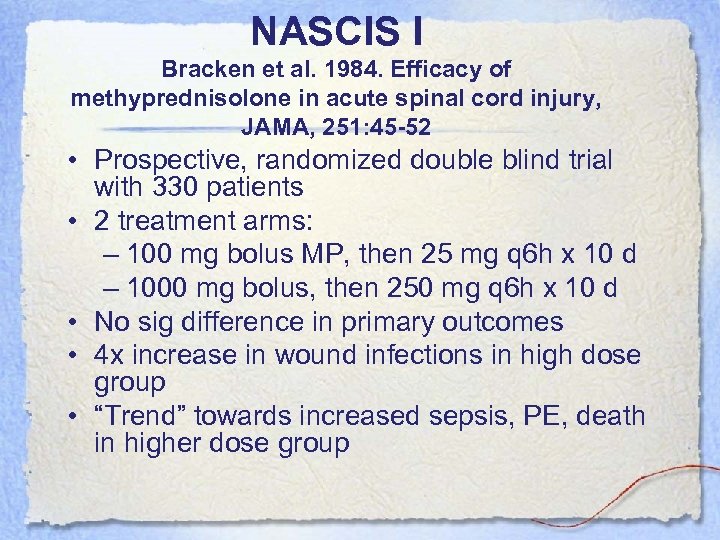

NASCIS I Bracken et al. 1984. Efficacy of methyprednisolone in acute spinal cord injury, JAMA, 251: 45 -52 • Prospective, randomized double blind trial with 330 patients • 2 treatment arms: – 100 mg bolus MP, then 25 mg q 6 h x 10 d – 1000 mg bolus, then 250 mg q 6 h x 10 d • No sig difference in primary outcomes • 4 x increase in wound infections in high dose group • “Trend” towards increased sepsis, PE, death in higher dose group

NASCIS I Bracken et al. 1984. Efficacy of methyprednisolone in acute spinal cord injury, JAMA, 251: 45 -52 • Prospective, randomized double blind trial with 330 patients • 2 treatment arms: – 100 mg bolus MP, then 25 mg q 6 h x 10 d – 1000 mg bolus, then 250 mg q 6 h x 10 d • No sig difference in primary outcomes • 4 x increase in wound infections in high dose group • “Trend” towards increased sepsis, PE, death in higher dose group